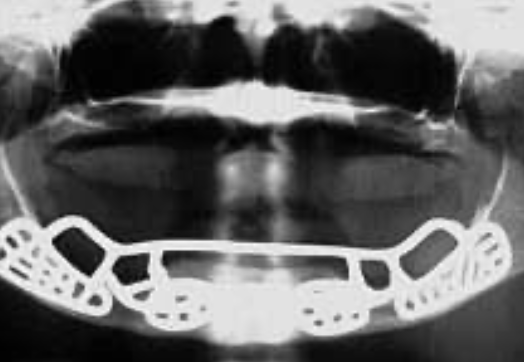

Titanium framework with HA coating

Panoramic view after placement